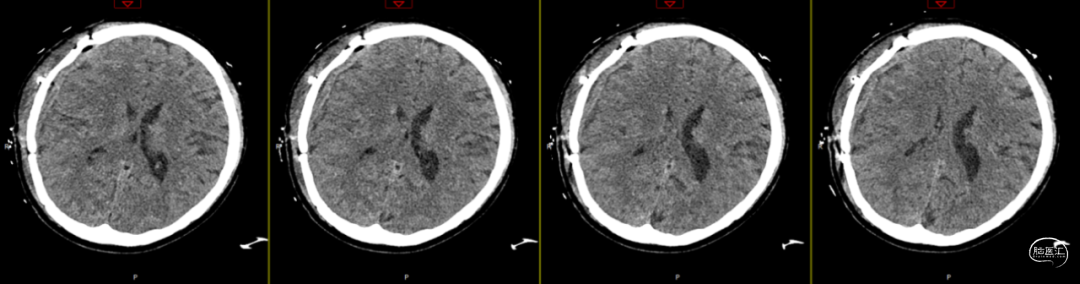

2024-07-21 08:58:55术后58天复查(如上图)。

术后58天颅脑磁共振平扫(如上图):右侧额顶颞部见斑片状异常信号,呈片状T1WI低、T2WI稍高信号影,T2FLAIR呈稍高信号,边界清,右侧额顶颞叶脑组织受压,DWI(b=1000)呈混杂高信号,相应ADC呈混杂高信号影。